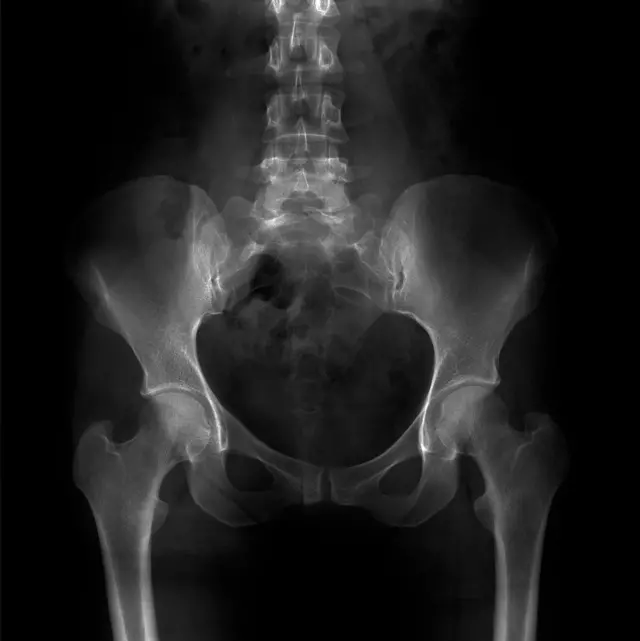

Pero el equipo observó otra cosa extraña. Si se crea un ratón con sólo la forma del gen TBXT con la sección excluida, pueden desarrollar una afección muy parecida a la espina bífida humana (cuando la columna vertebral y la médula espinal no se desarrollan correctamente en el útero, causando un hueco en la columna vertebral).

Anteriormente se habían relacionado con esta enfermedad mutaciones en el TBXT humano. Y hay que observar que otros ratones también presentaban diferentes defectos en la columna vertebral y la médula espinal.

El equipo sugiere que, al igual que el coxis es una secuela evolutiva de la falta de cola que todos tenemos, la espina bífida puede ser una secuela rara de la alteración del gen que sustenta nuestra falta de cola.